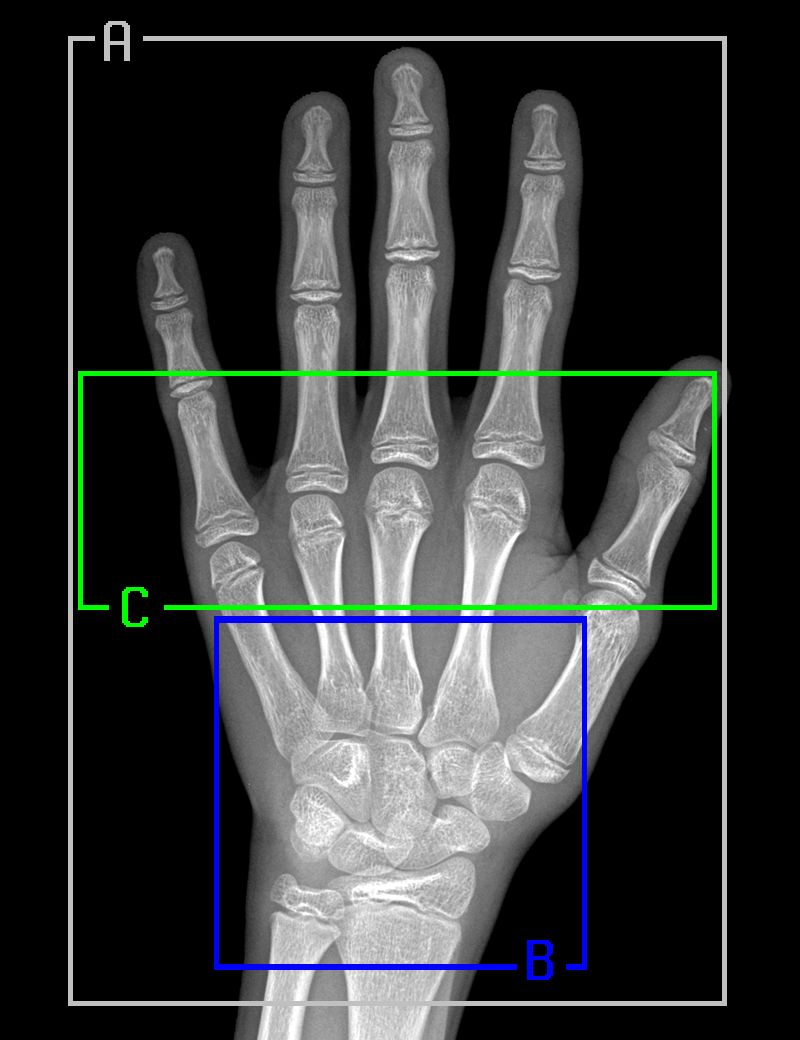

遵循 Gilsanz 和 Ratib 的《Hand Bone Age: a Digital Atlas of Skeletal Maturity》,我们从经过配准的放射影像中选择了三个特定区域,针对每一个区域训练了一个单独的模型:

1. 完整的手骨;

2. 腕骨;

3. 掌骨和近端指骨。

下图是真实放射影像中的上述区域以及相对应的分割样本: